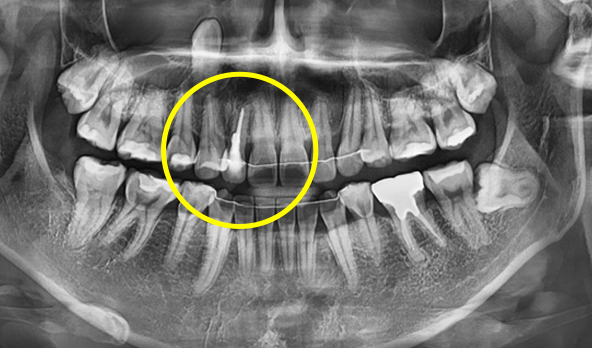

CT Precision Analysis & 3D Simulation

All preparations for surgery day are completed in advance during this phase.

• Precise analysis of alveolar bone and nerve location via CT scan

Precise analysis of

alveolar bone & nerve location via CT scan

• 3D analysis to determine implant placement position, angulation, and depth

3D analysis to determine

implant placement position, angulation & depth